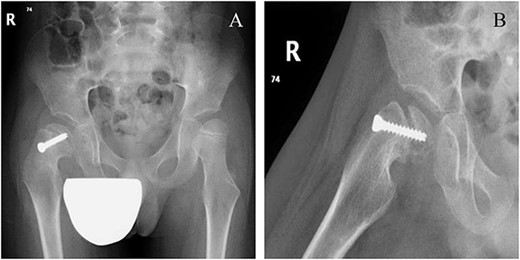

Six weeks following post-operative fixation: (A) pelvic anterior–posterior radiograph and (B) pelvic frog-leg lateral view radiograph.

A 5-year-old independent ambulatory Middle Eastern boy with CP who was born preterm and developed grade III intraventricular haemorrhage and periventricular leucomalacia and was on AEDs, including valproic acid (VPA) and levetiracetam (LEV), for >3 years and was controlled over the last year (no history of seizure attack) presented to the emergency room (ER) with right hip pain and inability to bear weight for 4 weeks; the patient had no history of fever or trauma. Physical examination shows a thin, the weight is 12 kg, the height is 101 cm, vital signs within the normal range, tenderness over the right hip, and external rotation of the right hip, with restricted hip mobility. A radiological study was performed ~3 months before the patient presented to the ER for follow-up examination of a left hip coxa valgus deformity with no apparent abnormalities in the right hip (Fig. 1). Initial imaging studies conducted in the ER showed an anterior–posterior view of the pelvic radiograph, revealing Klein’s line [13] not intersecting the capital femoral epiphysis (Fig. 2), and frog-leg lateral view radiograph of the right hip (Fig. 3) confirmed SCFE and Southwick’s slip angle [13] of ~50° (moderate). Laboratory findings were clear for endocrine and renal diseases or infection, except for low vitamin D (total 25-OH Vitamin D: 43.4 nmol/L), suggesting vitamin D insufficiency. The diagnosis was confirmed with clinical and radiological studies as right-sided unstable SCFE requiring surgery. Surgical intervention was performed with percutaneous in situ fixation using a single fully threaded 4.5-mm cannulated screw (Fig. 4). Postsurgical rehabilitation included non-weight-bearing right lower extremities for 6 weeks. Regular follow-up with serial radiology studies showed stable fixation with no migration of screw or further slippage at 6 weeks (Fig. 5) and 3 (Fig. 6), 15 (Fig. 7), and 36 months (Fig. 8). During follow-up, a painless range of motion in the right hip was observed, with full weight-bearing and resumption of his usual activities with no complaints.